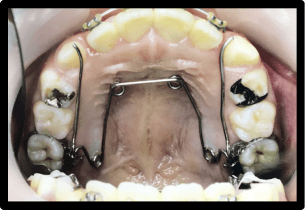

当院では以下のような装置に対応しています

固定式の装置

取り外しのできない固定式の装置となります。混合歯列期(乳歯と永久歯が混在している時期)に使用する事が多く、歯列の幅を広げることによって歯が生えるスペースを確保していきます。

BクワドヘリックスR

バイヘリックス

リンガルアーチ